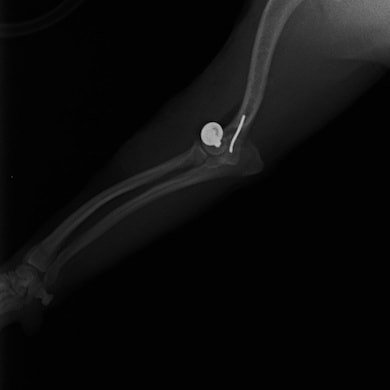

症例3:キルシュナーワイヤーのピンニングによる整復

ペルシャ猫 11ヶ月齢 雄

他院にて左大腿骨遠位の成長板骨折(salter-harrisⅠ型)が認められており、治療相談を目的として来院。当院にて、キルシュナーワイヤーを用いたピンニングにより骨折部位の整復を行いました。術後の経過は良好で、現在も経過観察中です。

術前レントゲン

術後レントゲン